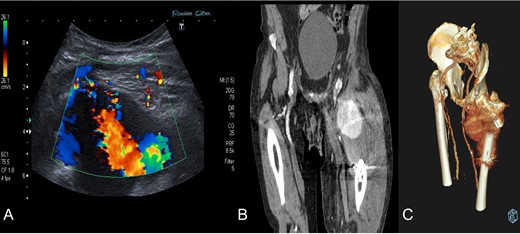

Diagnosis confirmation by Doppler ultrasound (A), shows hypoechoic lesion with turbulent flow inside with 5–6 cm of maximum diameter; and CT angiography (B) and three-dimensional reconstruction (C) that confirm a lateral circumflex artery pseudoaneurym branch of the deep femoral artery of 7,3 × 6,7 × 6 cm size.

We present a case of an 80-year-old institutionalized man, who suffered an unstable intertrochanteric fracture of the left hip, type 31.A2.1 (AO-OTA) due to a low energy accident after falling from his own height. The patient previous medical history included bipolar disorder, hypertension, DM, and right inguinal herniorrhaphy surgery. The patient underwent closed reduction and internal fixation with an intramedullary nail type Gamma3 (Stryker Trauma GmbH Prof. Küntscher-Str. 1-5 24 232 Schönkirchen, Germany) of the fracture during the first 24 hours after injury. The surgical procedure was performed without any intraoperative complications. He was discharged from the hospital on the sixth postoperative day, asymptomatic, with a postoperative hematoma in the left thigh, walking with a walking frame, with a postoperative radiographic control showing a correct nail placement without alterations and with an hemoglobin value (HGB) of 10.7 g/dl and a hematocrit value (HCT) of 30.8%. On the 18th postoperative day, he suffered a fall after having a syncopal episode, so he went to the emergency room and was admitted to the hospital for study. The hematoma in his thigh was evolving correctly, and the radiographs remained unchanged with respect to the previous ones. He was discharged two days later. One month after surgery, he returned to the hospital due to persistent pain, volume increase and progressive hematoma in the left thigh. The blood analysis showed an anemia (HGB 9.5 g/dL, HCT 29%). The pedia pulse was present and the posterior tibial pulse was weaker than the contralateral but also present. An X-ray showed a superior and medial displacement of the lesser trochanter compared to previous radiographs and a medialization of the femoral artery, visible because it was calcified (Fig. 1). A Doppler ultrasound was performed showing a hypoechoic lesion with turbulent flow inside compatible with pseudoaneurysm at the level of the deep femoral artery or one of its branches. The study was completed with a CT angiography that confirmed the presence of a pseudoaneurysm of 7.3 × 6.7 × 6 cm at the level of the deep femoral artery at the beginning of the lateral circumflex branch (Fig. 2). At that time, the patient was referred to the Interventional Radiology Service. The vascular lesion was immediately treated by femoral transcatheter embolization with two distal coils in the lateral circumflex artery measuring 3 and 4 mm (Axium 3D Medtronic 9775 Toledo Way Irvine, CA 92 618 USA) and proximal embolization by a liquid embolic agent, Onyx 34 (Covidien 106-108 Rue la Boetie 75 008 Paris, France).